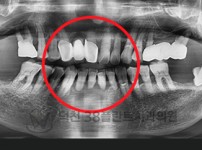

치료전후